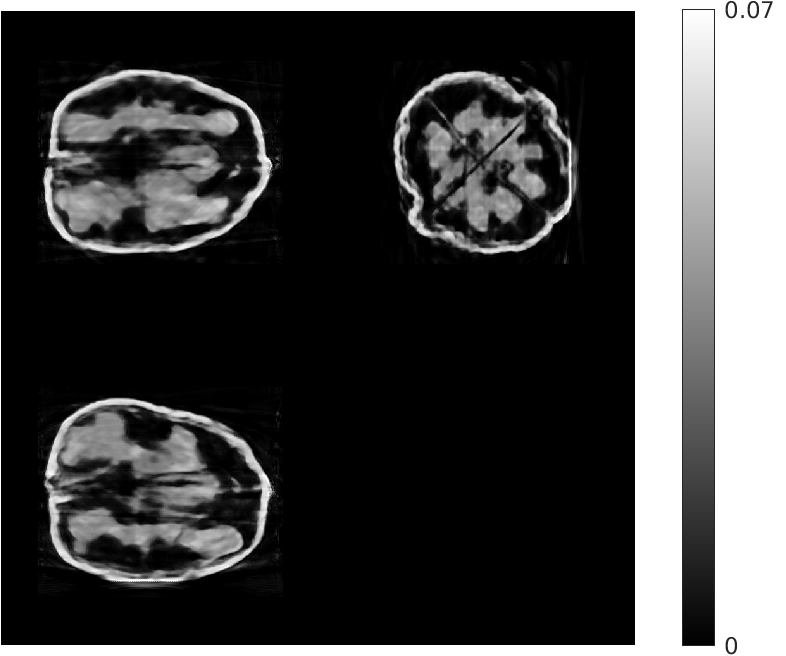

Fig. 5 shows walnut 1 from our test dataset being progressively reconstructed from 8 projections across the stages of our algorithm; as the stages progress, more features are restored in the reconstructed walnut, until the improvements become incremental. The residual streaking artifacts outside the walnut are mitigated in the reconstructions from the third and fourth stages.

| Stage 1 | Stage 2 |

![]() |

| (a) (MAE: 0.32) | (b) (MAE: 0.29) |

| Stage 3 | Stage 4 |

| (c) (MAE: 0.27) | (d) (MAE: 0.26) |